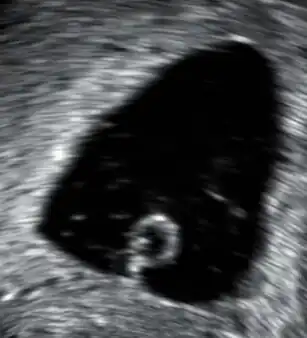

- Soms weet een vrouw nog niet dat de vrucht in haar buik is overleden. Vaak komt zij erachter bij de eerste echo, die vanaf 2007 tussen de 8e en 11e week van de zwangerschap wordt gemaakt door de verloskundige of de gynaecoloog. Het hartje van de foetus klopt dan niet, en soms is de foetus niet eens waar te nemen en ziet men enkel een lege vruchtzak. Vaak is in dit soort gevallen de foetus al een aantal weken dood. Men spreekt dan van een missed abortion. Er zijn dan verschillende mogelijkheden: afwachten tot de miskraam op natuurlijke wijze op gang komt; met behulp van medicijnen de uitstoting van het overleden vruchtje opwekken; een zuigcurettage laten doen door de gynaecoloog in het ziekenhuis.